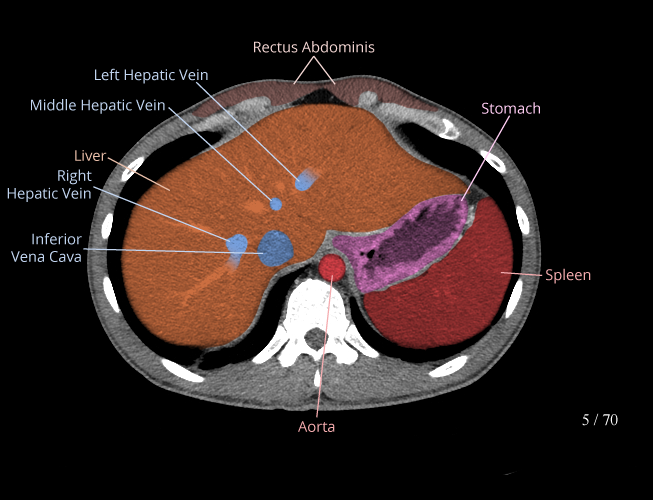

Body

Covers abdominal CT anatomy.